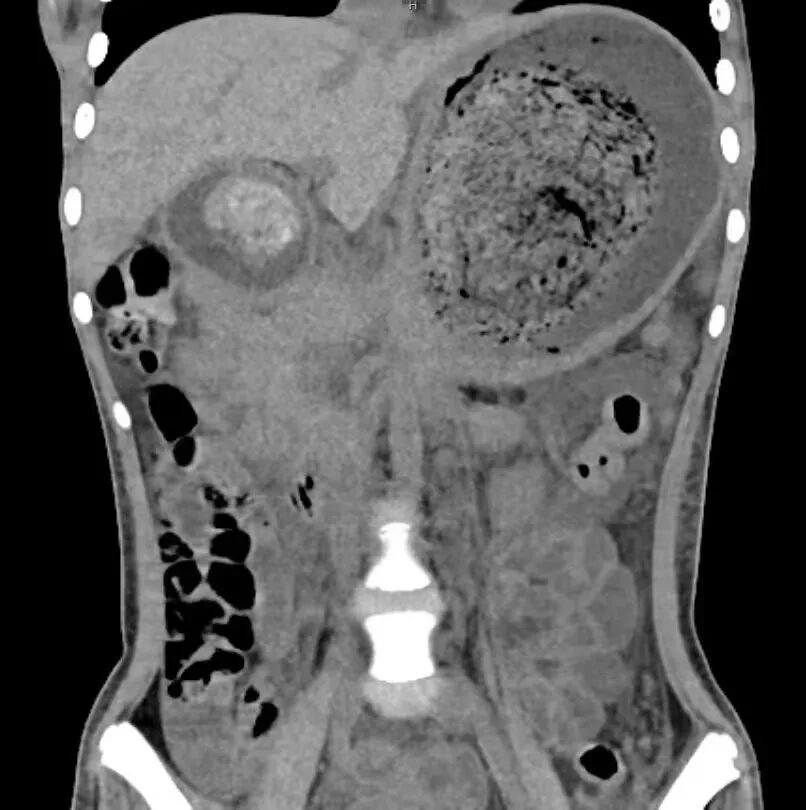

在儿科,接诊大夫为孩子进行了血液、影像检查,病因谜团才逐渐解开:小徐严重贫血,更让人不解的是影像检查显示,她的胃部有一个巨大的包块!

胃镜下的一幕,让医护人员心疼不已:巨大的包块竟是孩子“消失”的头发!密密麻麻、缠绕成团!

从患儿体内取出的巨大毛石

“孩子长期吞食的毛发与食物残渣混合在一起,已经变成了坚硬的毛石,占满了整个胃,就连十二指肠里都是。”鲍俊涛解释,这团巨大的毛石被完整取出来时,与胃、十二指肠形态一模一样,重达1.1公斤!